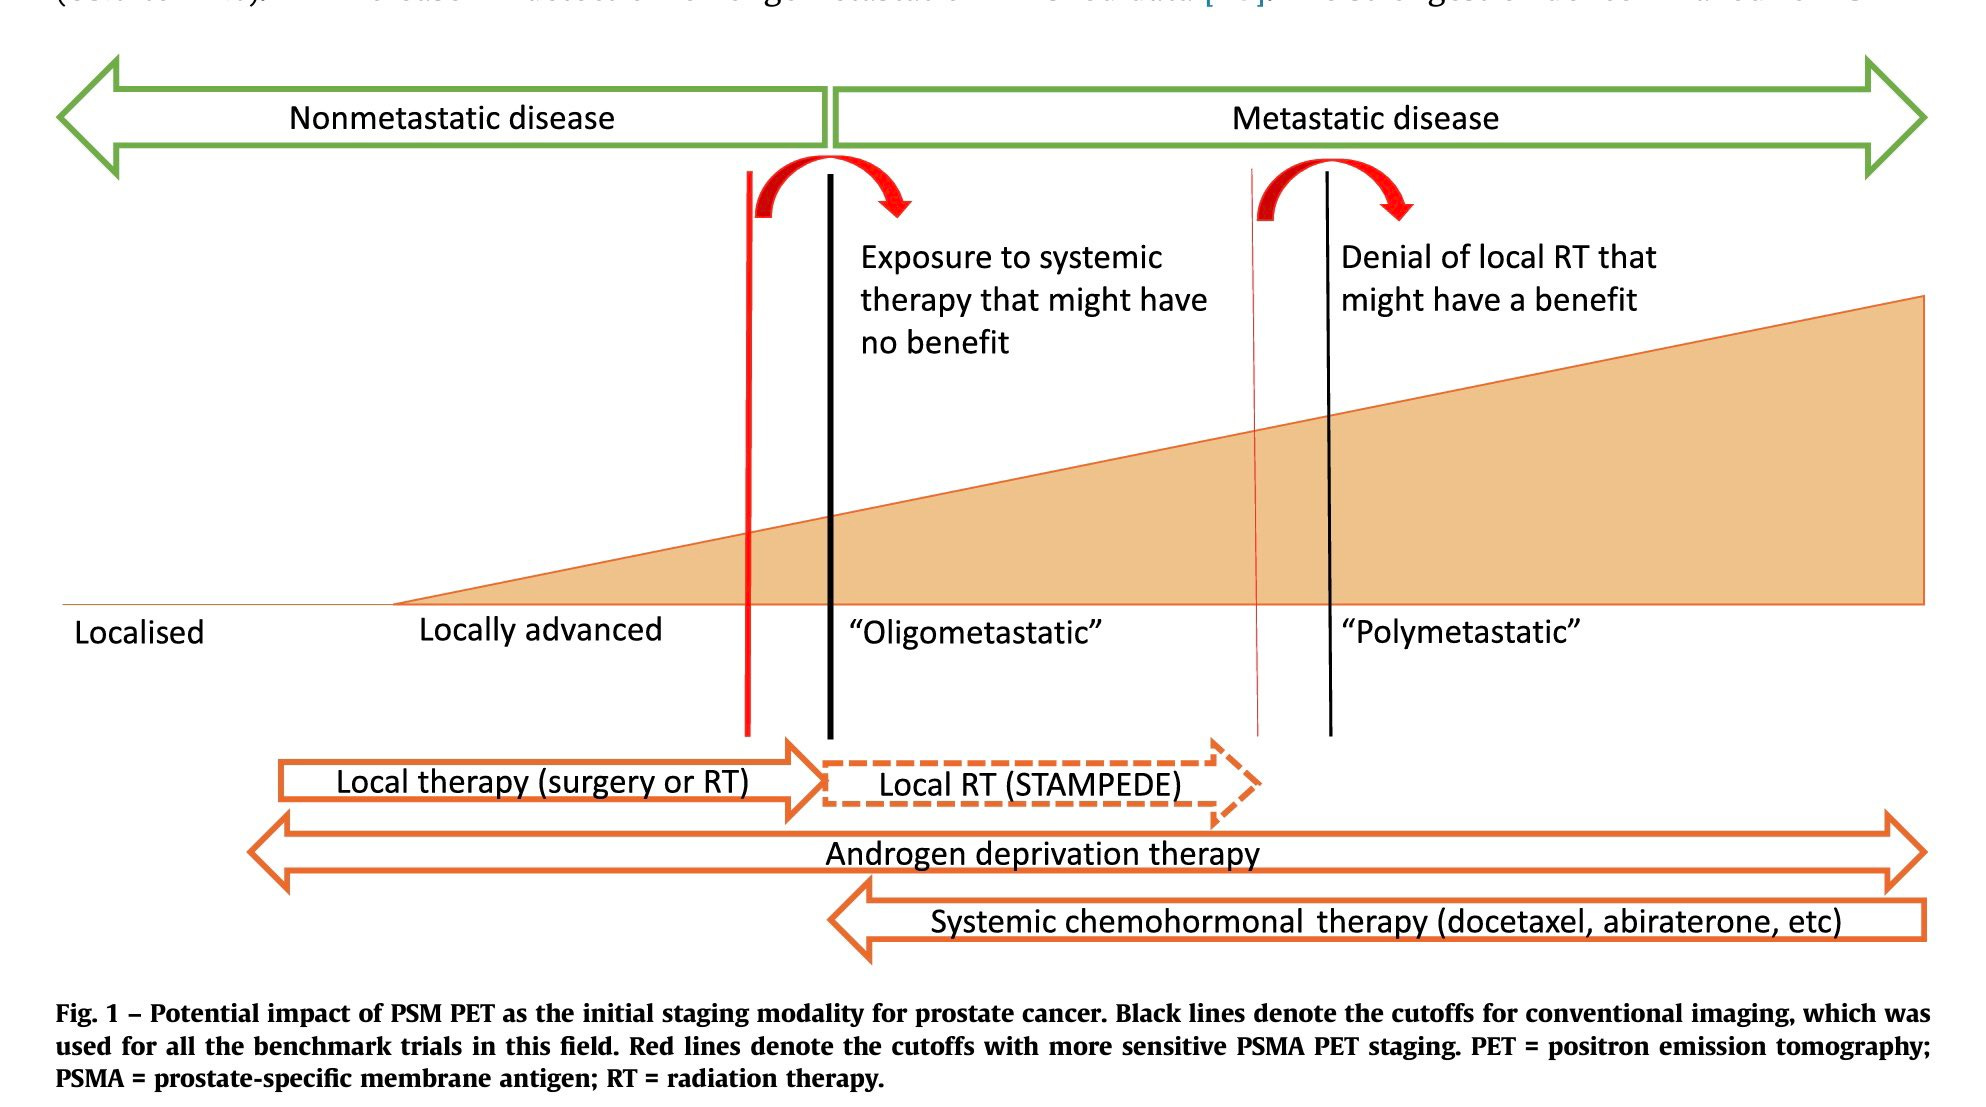

What To Do With a Positive PSMA PET and Negative Conventional Imaging in Patients With Prostate Cancer

PSMA pet scans: Just because it is more sensitive doesn't make it

Guiding management of therapy in prostate cancer: time to switch

PSMA-PET is rapidly changing the standard of care for prostate

Guiding management of therapy in prostate cancer: time to switch

Sequencing of Conventional and PSMA-PET Imaging in Prostate Cancer